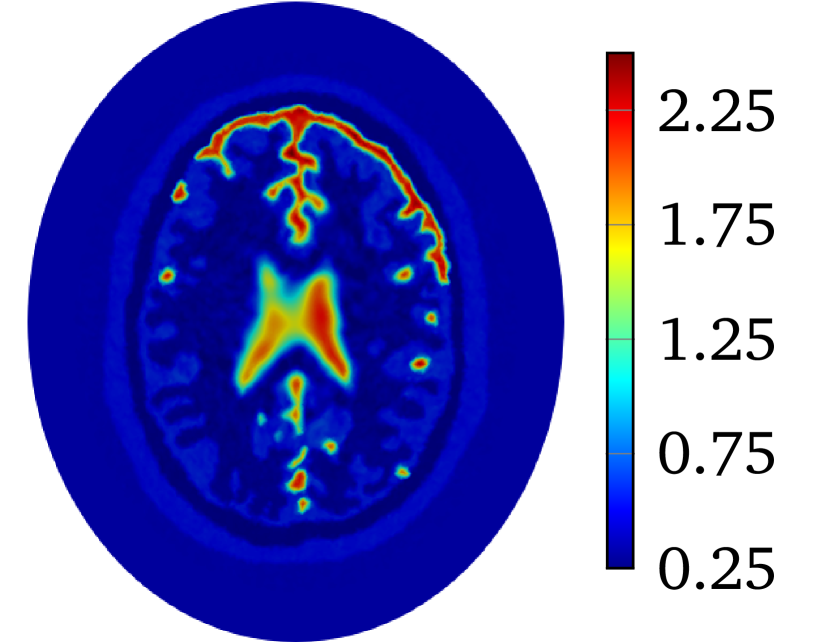

to produce with for 2D problem. The constant is selected so that . The value of is and for heart-lung model and human-brain model, respectively. The true smoothed distributions of for the two models are shown in Figure 2.

Though LM-SCEM performs well for reconstructing the conductivity map, its efficiency of the computation decreases quickly with the increase of measurements. Since EIT is not very sensitive to the change of interior conductivity, the electrical potential should converge faster than the convergence of the conductivity. The human-brain model is used here for numerical experiments with LM-SCEM. The elliptic domain is characterized with major and minor axes, and the domain is meshed with 36893 triangular elements. The parameters are given as , and . The current patterns and are used in the reconstruction. With noise, the iteration is terminated when or the maximum number of iterations equals 30. The reconstruction based on LM-SCEM is shown in Figure 7(a). of each current pattern is computed with SCEM and for -th iteration, easily follows then. The variation of the relative error and are shown in Figure 6(a) and Figure 6(b), respectively. As can be seen, slowly converges to . This error is much larger than the input noise level, this is mainly caused by the complexity of the phantom and the high contrast of among different tissues. But the potentials on the boundary for both and converge fast to a level of in few iterations. Therefore, the boundary potential converges much faster. This property is exploited here to accelerate the computation by mixing LM-SCEM and LM-DCM, as demonstrated in Algorithm 2. In this computation, the LM-SCEM is stoped when for all current patterns are smaller than . The LM-DCM is performed in the region with . The potential on is computed with SCEM and the reconstructed from LM-SCEM. The power density in can be reconstructed with the method introduced by Ammari et al [4]. However, it requires the knowledge on the deformation caused by the ultrasonic waves, therefore, we compute it with DCM instead. Noise with SNR is added, and LM-DCM is used for the reconstruction. The relative error is given in Figure 6(a). The conductivity map is reconstructed with in 30 iterations, and the result is given in Figure 7(b). Here, the time required for 30 LM-DCM iterations is about 20 minutes which is approximately the time needed for one LM-SCEM iteration. So the reconstruction efficiency is greatly improved, and better results are obtained. A similar computation with noise is further considered here. As seen in Figure 6(b), increasing noise does not influence much the convergence of the boundary potential, therefore, this mixed approach can be a good way to remove noise from the measured power density. With 40dB noise in the reconstructed power density in , the distribution of obtained with LM-DCM is shown in Figure 7(d). Comparing it to the results obtained with LM-SCEM, as shown in Figure 7(c), a better noise tolerance is observed in LM-DCM.